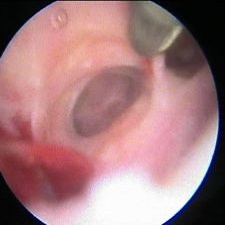

Nejčastější hysteroskopické nálezy

Hysteroskopické vyšetření při potížíchVyšetření